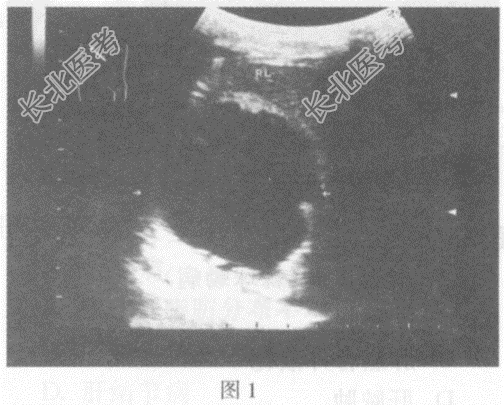

- 单项选择题临床资料:女性患者, 35岁,自述右上腹胀痛, 食欲不振。Casoni试验阳性。患者生活于牧区。

图2:同一患者肝右叶另可见4.6cm×5.1cm不均质回声区, 内回声由低-增强-强回声,轮廓清晰。